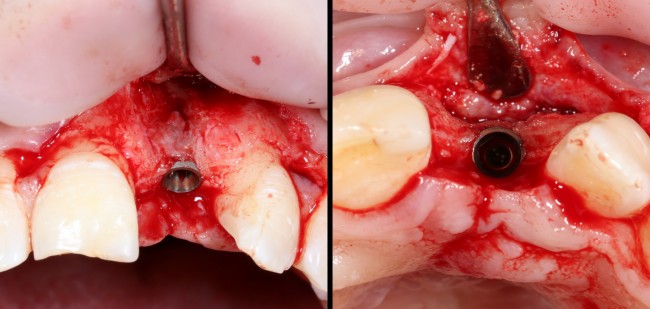

Делаем анестезию, разрез, скелетируем костную ткань:

На фотографиях хорошо видны оставшиеся после удаления объемы костной ткани. Давайте рассмотрим плюсы и минусы текущей клинической ситуации, применительно к нашему плану:

Фактически, альвеолярный гребень атрофировался по толщине примерно наполовину — это минус.

Зато с высотой все в порядке — это плюс

Немедленная нагрузка на имплантат невозможна — это минус. Почему? (см. Факторы…)

Достаточный объем кератинизированной десны, который даст нам возможность герметично запечатать послеоперационную рану — это, несомненно, тоже плюс. (вспомним факторы успеха остеопластической операции, часть III)

Ну и, оставшиеся объемы костной ткани позволят нам установить и правильно позиционировать имплантат — это главный плюс. А значит, мы обойдемся одной операцией вместо двух.

Продолжим нашу работу. Имплантат установлен:

Работа закончена? Отнюдь, нет. Теперь наша задача — восстановить утраченные объемы костной ткани вокруг импланта. Ибо, как вы видите на фото, его вестибулярная поверхность, практически, просвечивает. И, если ничего не делать, дальше будет только хуже.

Итого, наиболее оптимальным в данной ситуации оказалась направленная тканевая регенерация с использованием барьерных мембран. В качестве барьерной мембраны у нас будет Geistlich BioGide. Ее очень легко адаптировать и позиционировать:

А в качестве трансплантата — аутокостная стружка, которую я насобирал заранее из области угла нижней челюсти:

Начну с того, что BioGide — это лучшее, что есть сейчас на рынке, а остальные мембраны ей завидуют. Как и в случае с макродизайном имплантов, именно физические свойства определяют как удобство использования, так и возможность достижения нужного результата. Прочность, эластичность, легкая адаптация и адгезия делают ненужными использование фиксирующих пинов. Мы просто закрываем мембраной графт — и все, можно накладывать швы:

В другом ракурсе видно, какой объем тканей мы восстанавливаем:

и теперь швы. Наглухо (Фактор II):